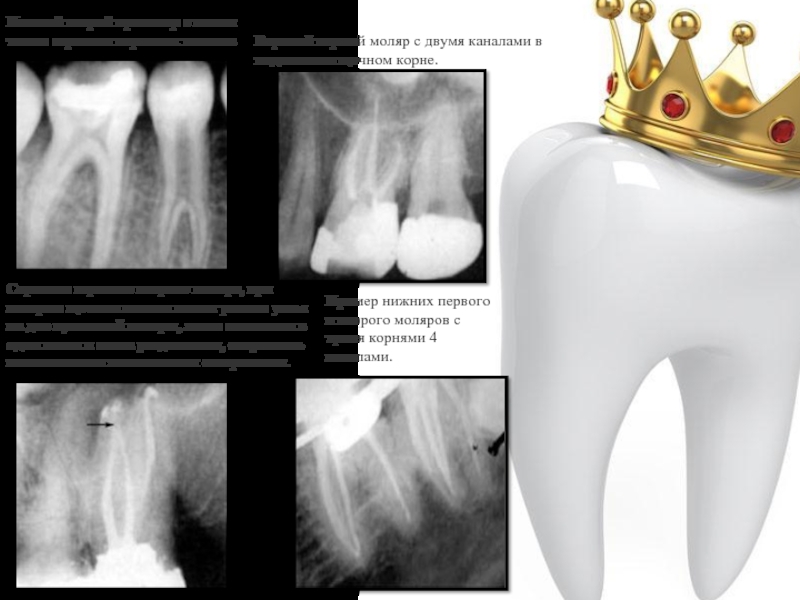

Слайд 8Нижний второй премоляр с пятым типом строения корневых каналов

Верхний первый моляр

с двумя каналами в медиальном щечном корне.

Строение верхнего второго моляра, при котором щечные каналы имеют разные устья на дне пульповой камеры, затем сливаются в один канал и снова разделяются, открываясь независимыми апикальными отверстиями.

Пример нижних первого и второго моляров с тремя корнями 4 каналами.